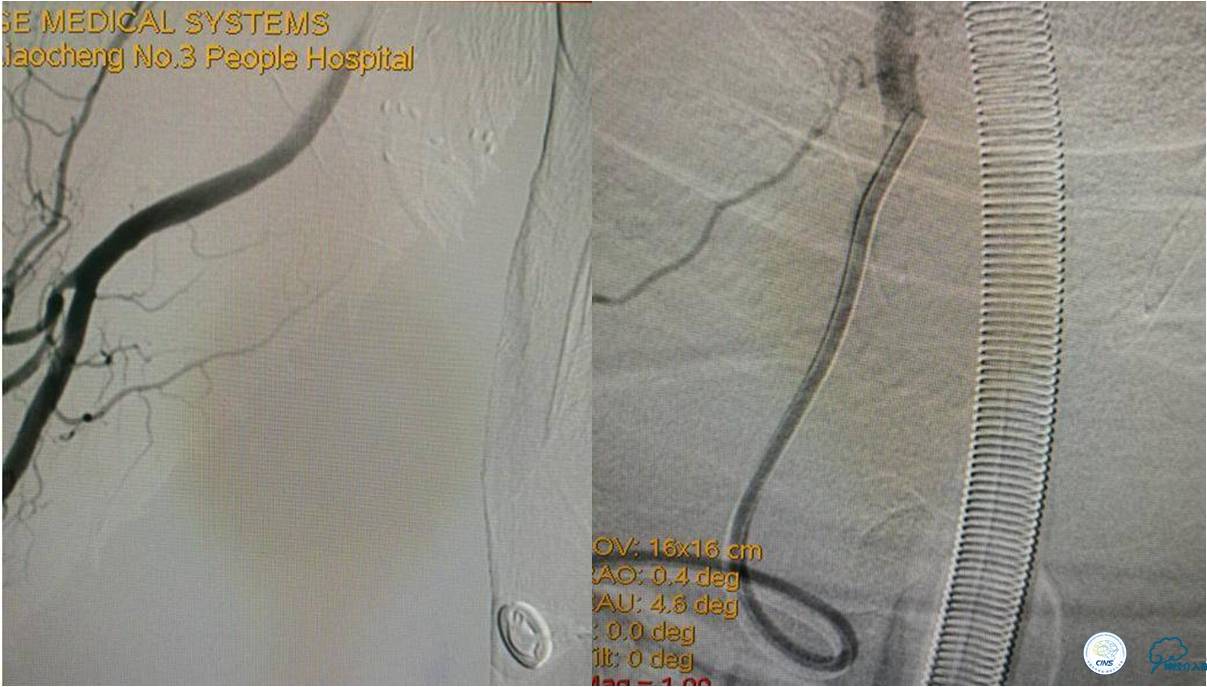

发病5.5小时给予股动脉穿刺

发现股动脉入路很差,考虑经桡穿刺。

》DSA资料(经桡动脉,5F导引导管)

★后循环取栓病人,若股动脉入路较差,可以考虑经桡动脉进行。